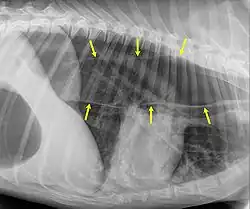

Megaesophagus, also known as esophageal dilatation, is a disorder of the esophagus in humans and other mammals, whereby the esophagus becomes abnormally enlarged. Megaesophagus may be caused by any disease which causes the muscles of the esophagus to fail to properly propel food and liquid from the mouth into the stomach (that is, a failure of peristalsis). Food can become lodged in the flaccid esophagus, where it may decay, be regurgitated, or be inhaled into the lungs (leading to aspiration pneumonia).[1]

An important distinction in recognizing megaesophagus is the difference between when a dog regurgitates or vomits. When a dog regurgitates there is usually not as much effort involved as when a dog vomits. Often when regurgitating, the dog will tip its head down and the liquid and/or food will almost appear to "spill out" of its throat.

One of the primary dangers to a dog with megaesophagus is aspiration pneumonia. Because the food stays lodged in the throat, it can often be inhaled into the lungs causing aspiration pneumonia. One way to avoid this is to make sure that every time the dog eats or drinks anything, that the dog sits for at least 10 minutes afterward or is held in a sitting up or begging position. This disorder has a guarded prognosis, however, a successful management technique is vertical feeding in a Bailey chair.[8]